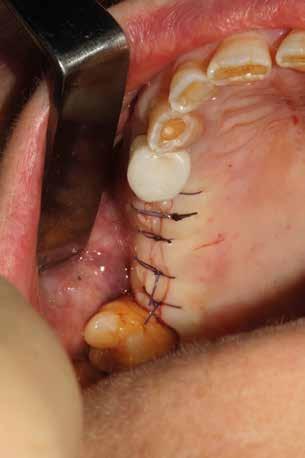

In ultimo, ha grande importanza anche il momento della sutura, la scelta dell’ago, del filo e la tecnica di legatura dei nodi (fatti alla giusta distanza gli uni dagli altri e con la giusta tensione); la riuscita dell’intervento dipende anche dalla qualità con cui vengono riavvicinati i lembi in modo da non ischemizzarne o danneggiarne i bordi. (Figg. 9-14)

Esempio chirurgico di accesso tra 2 elementi dentari con conformazione della cresta alveolare ampia. Incisione del lembo in cre sta senza scarichi laterali con sollevamento di 2 lembi, palatale e vestibolare; si può notare come quest’ultimo non si estenda oltre

Una incisione lineare netta si estende coinvolgendo minimamente il dente mesiale e maggiormente in direzione distale, consente di evitare l’esecuzione di incisioni di scarico che provocano una interruzione della vascolarizzazione maggiore, senza ridurre la visibilità del campo operatorio.